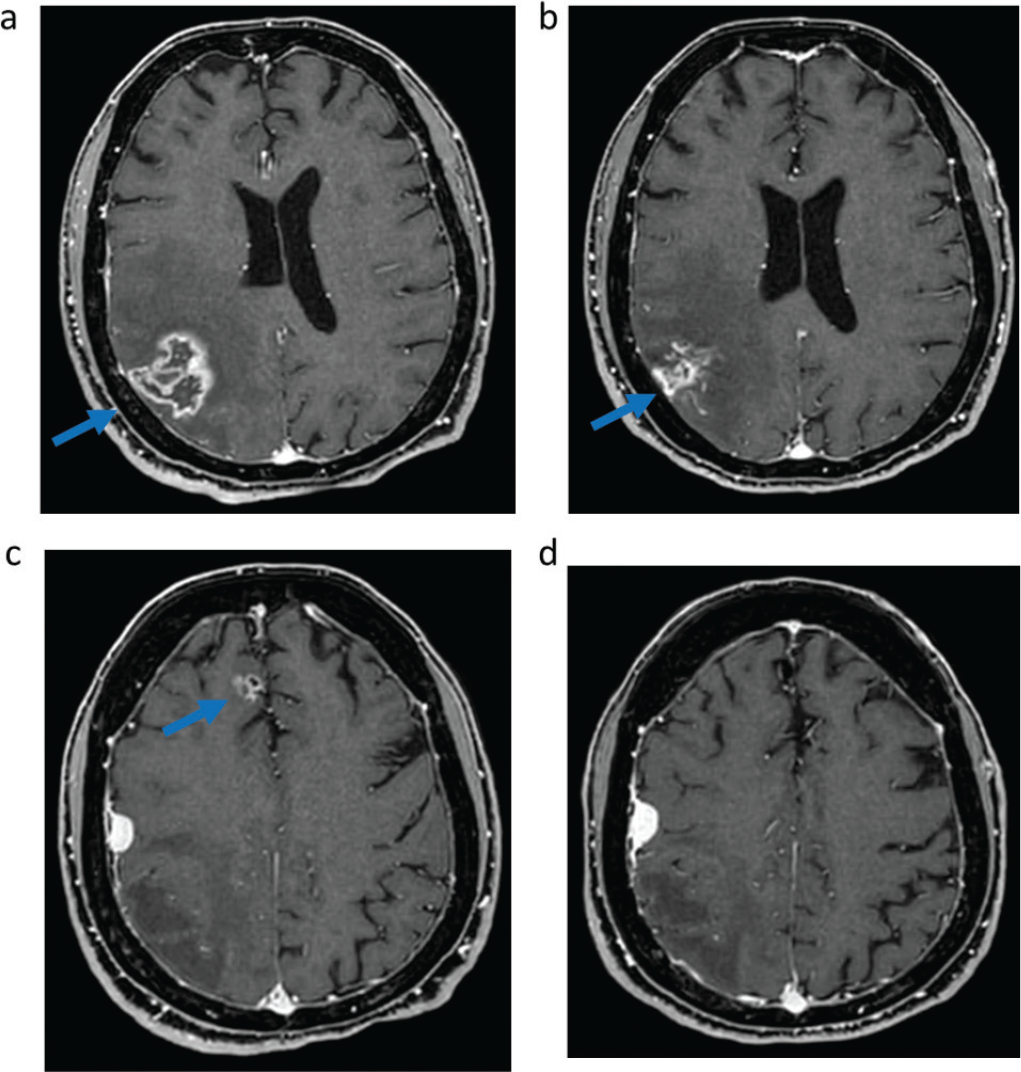

In March 2021 the patient experienced symptomatic intracranial disease progression, with a new brain metastasis in the right frontal lobe and increase in size of the other two known metastases and appearance of surrounding edema in the right parietal lobe, requiring steroid therapy. Positron emission tomography (PET)/computed tomography (CT) scan did not show extracranial disease. The patient was started on sotorasib, and the brain magnetic resonance imaging (MRI) after 2 months of treatment showed stability of the cerebellar metastasis, reduction in size of the previously treated parietal right metastasis with improvement of the surrounding edema, reduction in size of the previously untreated right frontal lobe metastasis, and no appearance of new brain metastases (Fig. 1). In March 2022 posterior fossa hemorrhage occurred due to bleeding of the cerebellar metastasis, which was treated with surgical evacuation of the hemorrhagic focus and metastasectomy. Histology examination of the cerebellar metastasis revealed radionecrosis with no residual viable cancer tissue. Treatment with sotorasib was continued and the disease remained stable until July 2022 when brain MRI showed oligoprogression due to increase in size of the right frontal metastasis, which was treated with stereotactic radiotherapy (24 Gy in three fractions). Sotorasib was continued and, after 27 months (May 2023), treatment is still ongoing, without safety concerns, and with stable intracranial disease at brain MRI and still no evidence of extracranial metastases at the PET/CT scan.

Fig. 1 - Intracranial response to sotorasib assessed with magnetic resonance imaging. T1-weighted imaging of right parietal metastasis before (A) and after (B) 6 months of sotorasib; Fluid-attenuated inversion recovery of right parietal metastasis surrounding edema before (C) and after (D) 6 months of sotorasib; T1-weighted imaging of right frontal metastasis before (E) and after (F) 6 months of sotorasib; T1-weighted imaging of right cerebellar metastasis before (G) and after (H) 6 months of sotorasib.